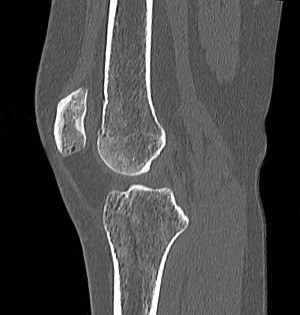

Локтевой сустав

Коленный сустав